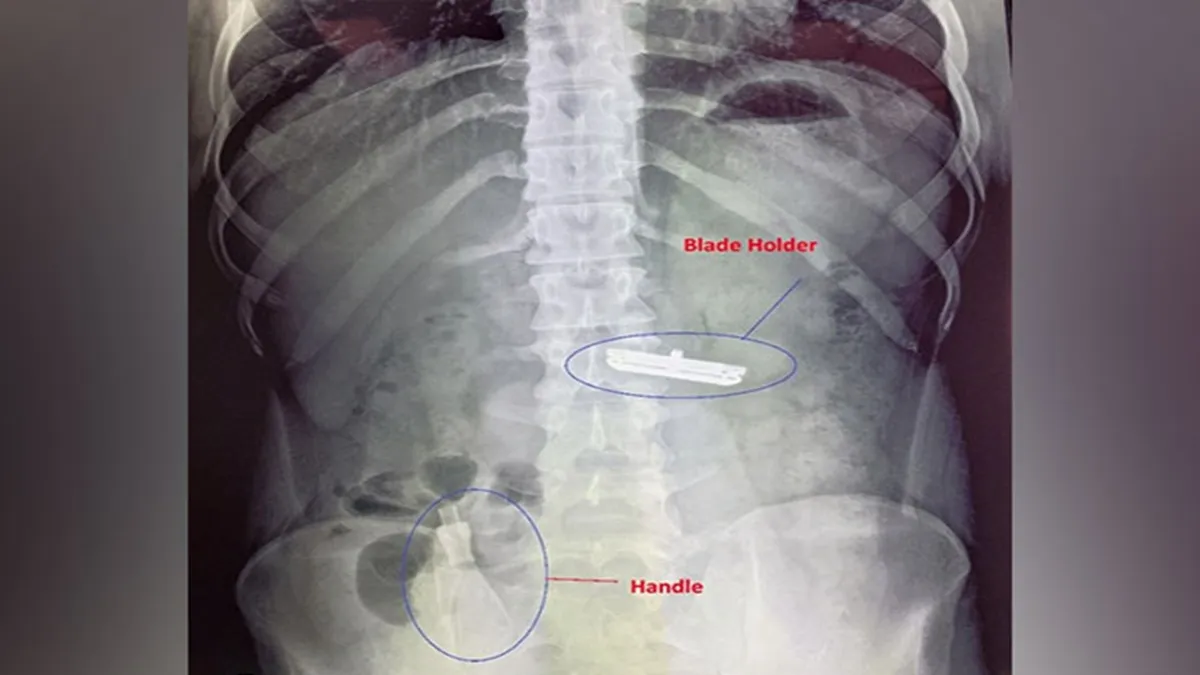

Delhi: In a case highlighting the interplay of mental health and surgical emergencies, doctors at a private hospital in Delhi successfully treated a 20-year-old man who swallowed a shaving razor in a fit of anger following a quarrel with his father. The young man, suffering from depression and suicidal tendencies, ingested the razor in two parts- the blade holder and the handle- posing a threat to his life. His father also suffers from a mental illness, adding to the family's challenges.

Scans showed that the blade holder had lodged in his stomach, while the handle had moved to the large intestine. A team of surgeons, led by Dr Tarun Mittal and including Dr Anmol Ahuja, Dr Shresth Manglik, Dr Rakesh S, Dr Karthik Krishna and Dr Tanushree Nahata, performed a two-step procedure.